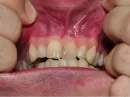

Мне 27лет. 5 лет назад на 1-ке, зуб да этого 2 раза пломбировался, у меня удалили кисту (резекция корня). Месяц назад над этим зубом, на десне вылез свищ, из него идет гной при надавливании.

Испугался, что повторная киста и зуб придется удалить. Сделал снимок, в районной стоматологии хирург сказал кисты нет, терапевт тоже самое. Также сказал проводить полоскания содо-солевым раствором и тогда со временем затянется, и что этот свищ - мое спасение, что он вот так вышел. Но у меня все равно недоброе предчувствие, так как уже месяц я с этим свищом (хотя каюсь, полощу редко).

Наличие свища говорит, что в области верхушки корня идет воспалительный процесс в стадии гнойного воспаления.

Возможно, придется проводить повторное эндодонтическое лечение.